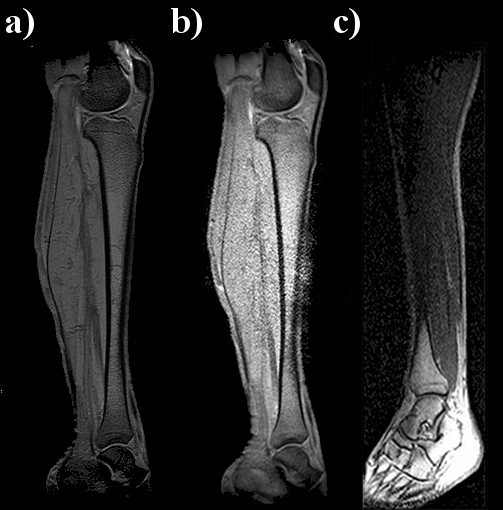

T1-weighted images of a healthy volunteer’s entire leg were obtained using: a) the whole-body coil, b) the PPWG and c) a pair of RF coils are shown in Fig. 9. As shown, good quality images were acquired with this simple waveguide and the two circular-shape flexible coils. The FOV used to cover the entire leg is much larger than the coil size (11 cm diameter), and the B1 field is not attenuated along the entire leg; moreover at the waveguide ends, a signal increase is observed. An extra 5 cm can also be gained with the waveguide scheme. It is also important to highlight that one single FOV covering the entire leg was applied such that digital processing was not necessary as reported in [16]. Additionally, the leg image acquired with the pair of single RF coils (Fig. 9.c) shows really poor quality image. The regions near the two surface coils show very good contrast and a good image quality compared to the central region. Nevertheless, an increment in the noise level is also observed in the waveguide image (Fig. 9.b)) for the central region; this is likely due to the fold over effect caused by a FOV whose size is greater than the common FOV sizes used in clinical practice and, no fold over suppression was applied.

[Uncaptioned image]

Figure 9. T1-weighted images of a human leg acquired with the whole-body birdcage coil (a) and PPWG + pair of RF coils (b) and the pair of coils only (c). The image acquired with the twMR approach shows an increment of noise at the centre of the leg not present in the other two leg images. The image obtained with the pair of coil shows a really poor signal compared to the other images. An evident signal contrast between the central and the foot regions can be appreciated: the higher image intensity can be explained by the close proximity of the coil to the foot (Fig. 1.c).

Another possible source of error is the image reconstruction scheme which is not the best suited for twMRI experiments. This is a matter of concern and deserves a thorough investigation. However, the performance of the travelling-wave approach shows a great potential for imaging large FOVs. The images in Fig. 9.a) and b) were normalized to the standard deviation of the image for comparison purposes and shown in Fig. 10. Comparison plots of image intensity distributions were also computed using the image data from Fig. 9 for both images. Fig. 9.c) image was shows very poor image quality and it was not used in the image comparison.

Figure 10. Comparison of normalized images acquired with the whole-body birdcage coil (a) and PPWG + pair of RF coils (b). Central region of (b) image is greater that the other leg image. Noise is probably due to the fold over effect and that no fold over suppression was applied.